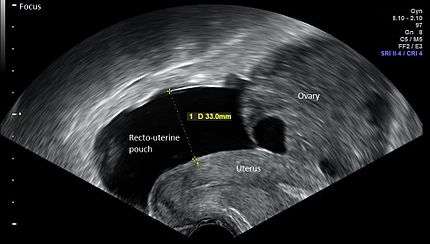

![]() ![]() Vaginal ultrasonography in the sagittal plane in a woman with mild OHSS, showing a 33 mm wide anechogenic area behind the uterus in the recto-uterine pouch, which means there was ascites, that is, free fluid in the peritoneal cavity. Normally, there is up to 5 ml of fluid in the recto-uterine pouch,[3] corresponding approximately to an area up to 10 mm wide. The ovary measured up to 6.5 cm in diameter. |